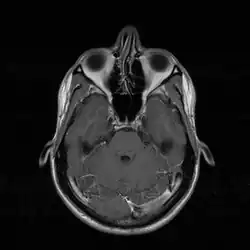

Skrzywienie przegrody nosowej (łac. deviatio septi nasi) – wrodzona lub nabyta deformacja przegrody nosowej.

Nabyte skrzywienie przegrody nosowej powstaje najczęściej na skutek przebytego urazu nosa w większości przypadków współistniejącego ze złamaniem kości nosowych.

Zgodnie z teorią opracowaną przez Vernona D. Graya, wrodzone skrzywienie przegrody nosowej powstaje na skutek nieprawidłowego ułożenia płodu w macicy i urazów okołoporodowych. W swojej pracy Gray wykazał częstsze występowanie skrzywienia przegrody nosowej u dzieci pierworódek oraz w przypadkach, w których drugi okres porodu trwał ponad 15 minut. Odnotował również zależność między kierunkiem skrzywienia przegrody nosowej a kierunkiem IV zwrotu płodu[1].

Opisana przez Graya hipotetyczna linia, tzw. linia Graya, łącząca kolec nosowy przedni z dziobem klinowym kości klinowej stanowi umowną granicę: do przodu i ku górze, od której większość deformacji przegrody nosowej ma przebieg pionowy, do dołu i ku tyłowi zaś − przebieg poziomy[2].